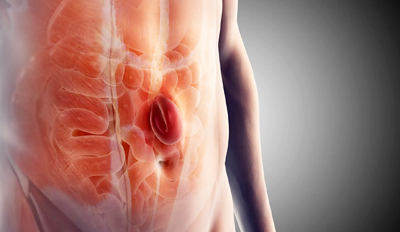

Laparoscopic surgery is a minimally invasive technique performed through small incisions using a camera, resulting in less pain, smaller scars, and faster recovery.